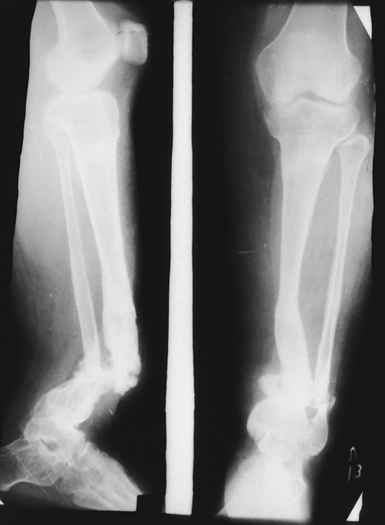

Глубокоуважаемые коллеги женщины! Поздравляем с праздником ВЕСНЫ, Международным женским днем - 8- МАРТА, здоровья , благополучия и успехов во всем! Ребенок 1г, мальчик, от первой беременности, родился без патологии весом 4кг, родители травму исключают, постепенно заметили деформацию н/з голени, которая начала увеличиваться . Брак родственный. Об-но; имеется угловая деформация открытым углом кзади на уровне н/з голени, ригидная , коррекции поддается мало. Функция коленного и г/с суставов не нарушены. Уважаемые детские ортопеды! Почему такое упорное молчание ортопедов! Я искреннее прошу прошения , если можно , мы нуждаемся в Ваших советах! План лечения; этапное, дистракционный аппарат, коррекция деформации, остеотомия в/з б/б кости, удлиняющая дистракция в обл остеотомии с одновременной компрессией в обл псевдоартроза и наблюдение , дальше по обстоятельству Вопросы; . 1. В каком возрасте можно начинать лечение, какие еще варианты лечения? 2. На Р-грамме как будто имеется недоразвитие дистального эпиметафиза м/берцовой кости, тогда что можно делать? С уважением Абдурашид.